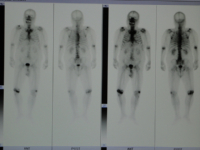

核医学装置 骨の全身像 心臓の断層像